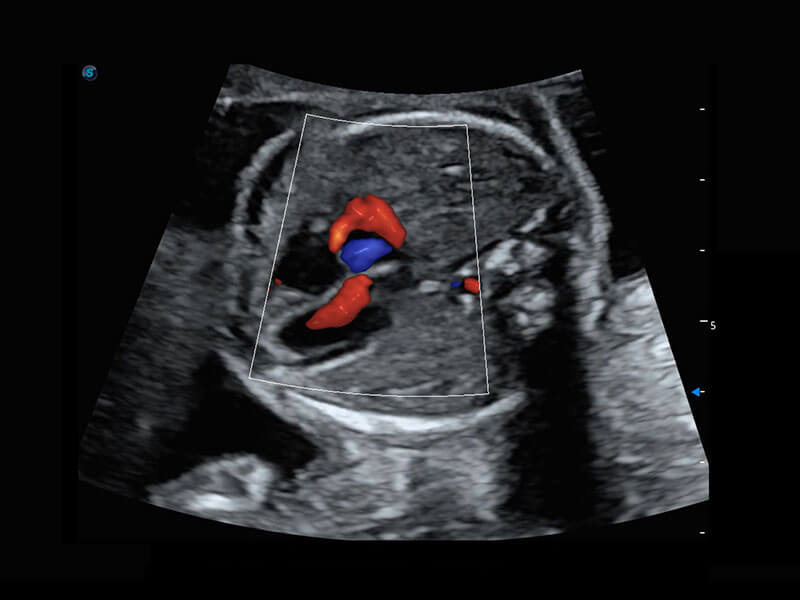

胎儿体循环

P60搭载一系列胎儿心脏成像技术,实现精细的胎儿心脏评估。

胎心容积成像